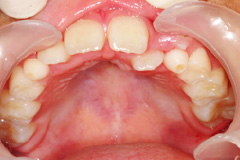

では小学生低学年の1、2年生ですと、まだ生え変わりが始まったころで、乳歯がたくさん残っております。

このころに上顎と下顎の大きさの不調和だったり、顎と歯の大きさの不調和を整えていくことが、永久歯を生やすための準備をすること、つまり予防的矯正につながります。

個人差はありますが、3年生位にスタートすることが平均的にスムーズに歯の交換を行うための適齢期といえるでしょう。ただし受け口の場合は6歳の前後には一度検査を行うことをおすすめします。